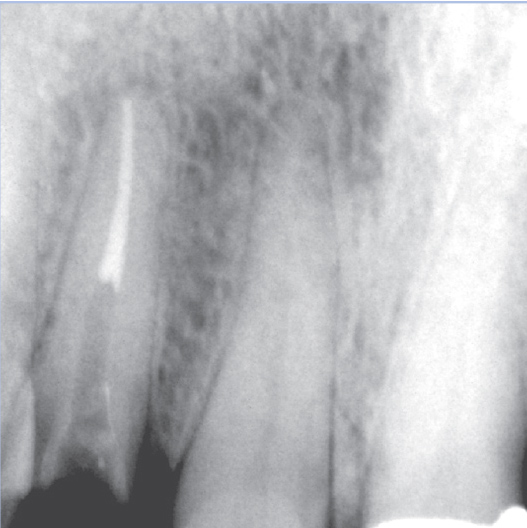

Before

Before Root Canal treatment